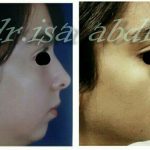

– متخصص جراحی فک , پلاستیک صورت و بینی

جراحی فک , پلاستیک , صورت وبینی

جراحی ترمیمی و زیبایی فک و صورت و جمجمه و گردن